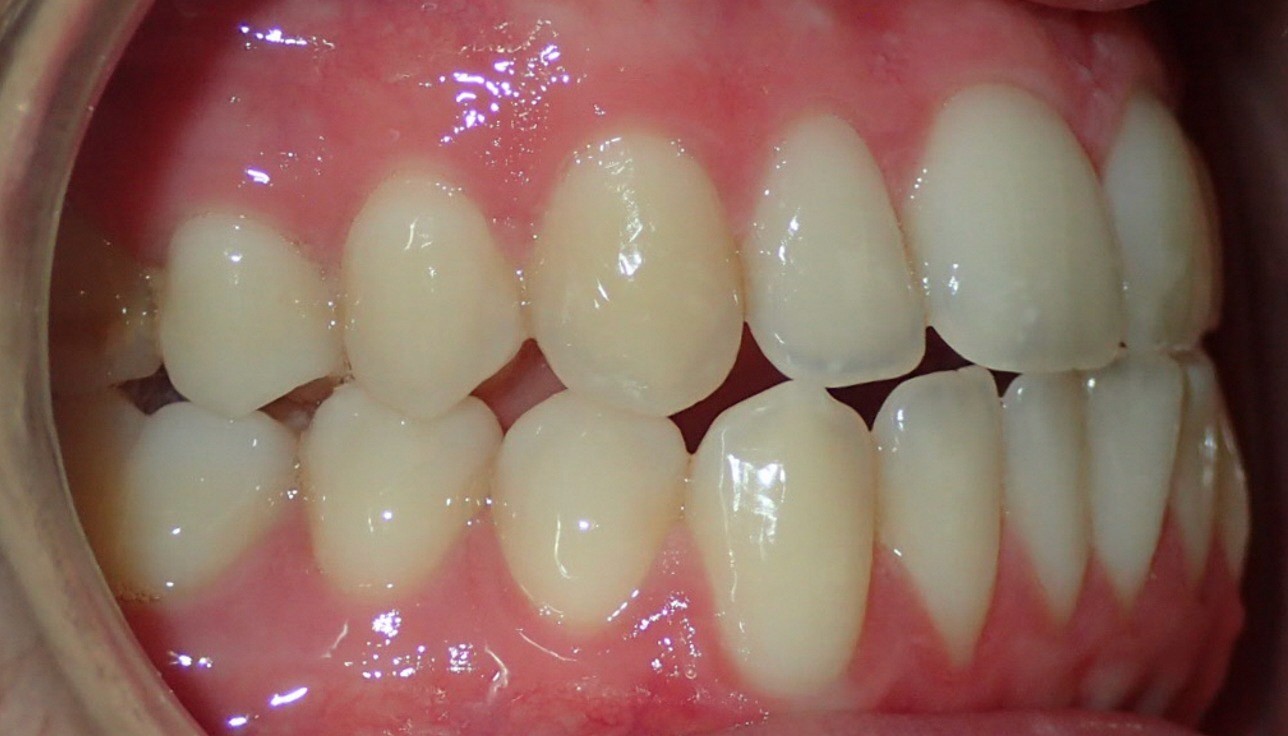

Final results

INTRAORAL